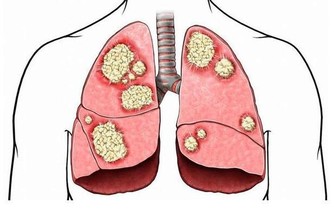

頸動脈硬化、腦動脈硬化,動脈管壁損傷,形成斑塊,導致管腔狹窄,血流不暢,影響腦供血,腦供血不足,腦組織得不到足夠的營養,就是出現頭暈的症狀,長期腦供血不足,腦組織會慢慢萎縮,影響智力,發展為血管性癡呆。

頸椎病主要是由於長期低頭或者外傷導致頸椎發生病變,包括頸椎骨質增生、椎間盤突出等等,導致椎管狹窄,也會導致椎動脈受到擠壓,椎動脈想腦部延伸,成為大腦供血主要干支,椎動脈狹窄,自然會使得腦組織缺血,也會產生頭暈。

3、腦梗塞

有腦梗賽病史的患者多有頭暈的臨床表現,頭暈表現為持續性,是腦血管梗阻後,相應區域內腦組織供血不足導致的。